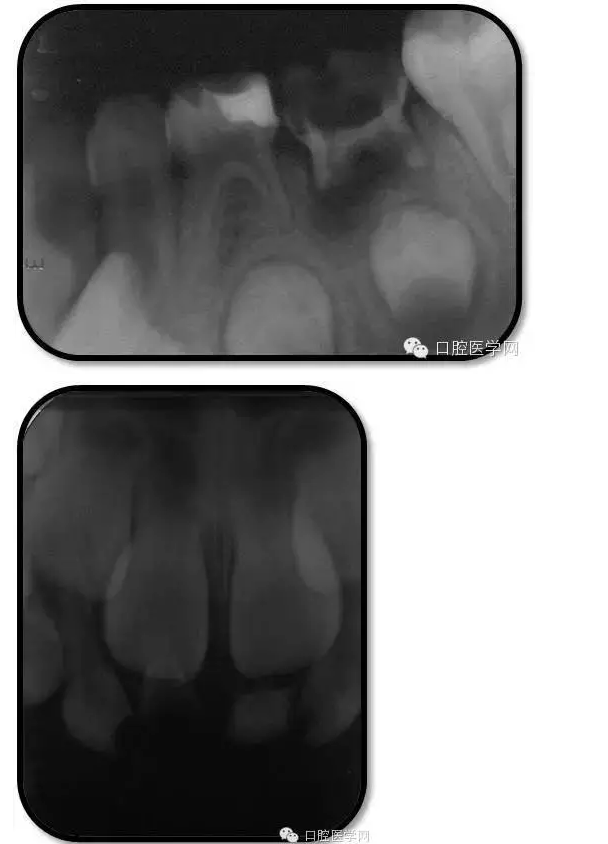

臨床檢查: 75OL齲洞, 舌側(cè)牙體完全劈裂斷端齊齦,探及大量軟化腐質(zhì)。頰側(cè)牙齦紅腫見瘺管,擠壓大量溢膿。叩(±),不松動。X線:75根管空虛,牙根吸收約1/2,根尖周及根分歧大面積透射影,35發(fā)育4期,骨硬板尚連續(xù);51殘根,唇側(cè)牙齦瘺管,叩(±),不松動。X線:51牙根吸收約1/2,根尖周低密度影。

85O、84DO充填體邊緣不密合,叩(±),不松動。84頰側(cè)牙齦略紅腫。X線:84遠中根及髓室底完全吸收,根分歧透射影,近中根內(nèi)側(cè)見外吸收,44上方骨硬板連續(xù)。85近中根完全吸收,髓室底吸收,根分岐透射影,遠中根管內(nèi)見根充影像。45發(fā)育4期,骨硬板連續(xù)。

QQ圖片20150728144435.png

QQ圖片20150728144451.png